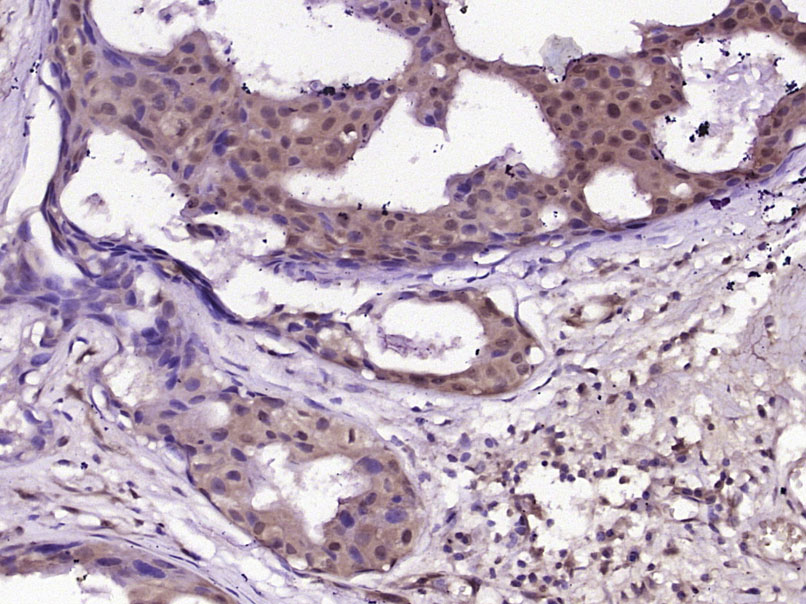

Paraformaldehyde-fixed, paraffin embedded (Human breast carcinoma); Antigen retrieval by boiling in sodium citrate buffer (pH6.0) for 15min; Block endogenous peroxidase by 3% hydrogen peroxide for 20 minutes; Blocking buffer (normal goat serum) at 37°C for 30min; Antibody incubation with (phospho-B Raf (Thr598)) Polyclonal Antibody, Unconjugated (bs-12557R) at 1:400 overnight at 4°C, followed by operating according to SP Kit(Rabbit) (sp-0023) instructionsand DAB staining.